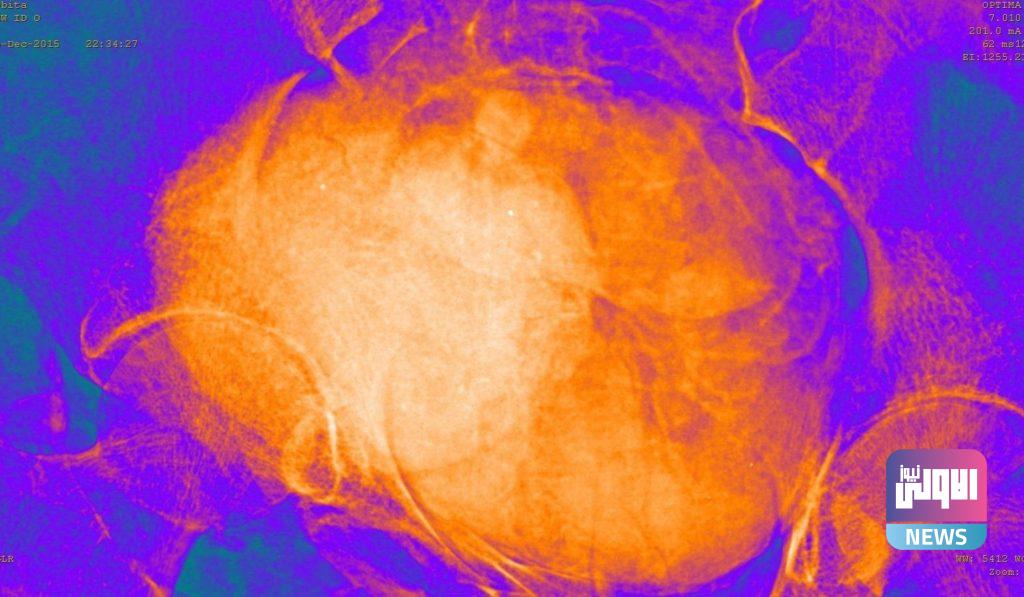

وأوضح التقرير أن المومياء خضعت لمجموعة من الفحوصات المقطعية، والأشعة السينية، والتصوير ثلاثي الأبعاد، مما مكن من فحص الجنين بدقة، حيث أثبتت الفحوصات أن المرأة كان في الأسبوع 26 أو 28 من الحمل.